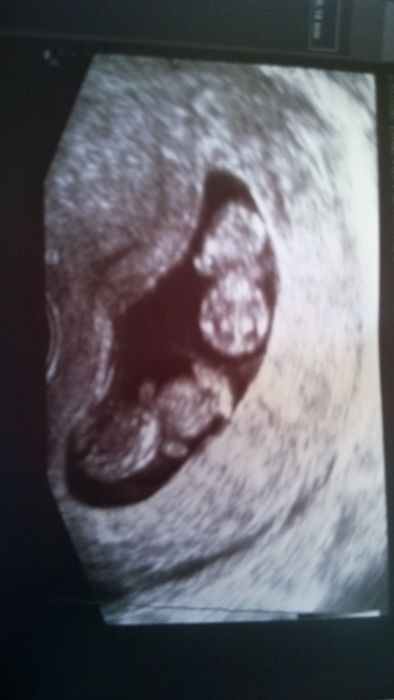

Ahoj holky, Tak hlasim, ze za sebou mame úspěšnou kontrolu. Mimca jsou v poradku, jedno 28mm a druhy 27mm :) Jen doktor je hulvat. Řekl mi, ze je to rizikovy a pak se me zeptal, jestli nechci radši jedno zabit, ze by to bylo bezpevnejsi. Ja myslela, ze zabiju jeho. No u nej sem byla stejne naposled, od priste uz musim na specializovaný pracoviště, protože nas budou víc hlídat. Dnes mi vzali komplet krev a 10.12. screening :) do té doby jeste dve kontroly, prvni v pondeli pro prukazku :) Moc Vam všem držím palce, neni lepsi pocit, nez koukat, jak se tam ten drobek vrtí! A Mmky na tchyni se kasli, ted jste nejdůležitější vy dva. Opatruj se

Adel veliká gratulace!!Co že ti to řekl???to snad není možný..je to strašný..to jsem teda ještě nezažila...hulvát jeden!!Ještě že jdeš jinam ...moc pěkná fotecka z utz.Evi řekla bych ji pravdu..že ji u sebe doma nechci.. měla by se nad sebou zamyslet...

Adél ta fotka je naprosto kouzelná

takový dvě miminečka nikdy sem ftku dvou miminek neviděla to je fakt krásný ...kolikátý jsi týden? a doktor jak píšou holky ne hulvát ale prase protože todle nemá právo říkat pokud tam není nějaký riziko nebo jaká koli jiná příčina která by ohrožovala na životě Tebe nebo děti. mmky možná by ses když pláčeš neměla schovávat před přítelem on by pak jistě sám ppřišel na to že trávit tak hezký svátek jako jsou vánoce s takovou tchýní je pro tebe stres ...už jen ten pocit že by měla dojet by tě stresoval a tak prostě tyto vánoce když se tchýně chová jako prase č2 první je doktor od Adél tak prostě at si pořídí na vánoce štěnátko nebo já mám kotátka a bude mít hned společnost

Děkuju holky, on je to debil celkove. Jinak on to myslel tak, ze dvojky jsou rizikové vždy, kor jednovajecny. Tak ze proc riskovat :/ Ja uz o tom četla i na nějaký diskusi...nekdo je toho schopen, proste nechtěj dvojčata, tak doktor tomu slabsimu strikne jed. Fuj, me je hrozne jen z te představy. Vlasti dekuju :) jsou to uz opravdu mimca. Dnes je to 9tt+5, další fotku budu mit asi az toho 10.12. tak se pochlubim, jak rostou. Snad to i pres to vecne straseni zvládneme vsichni tři az do konce ;) Pro mě jen jediná "nevýhoda" je , ze se budeme muset stěhovat. Do dvougarsonky tři dětský postýlky nenarvu :D